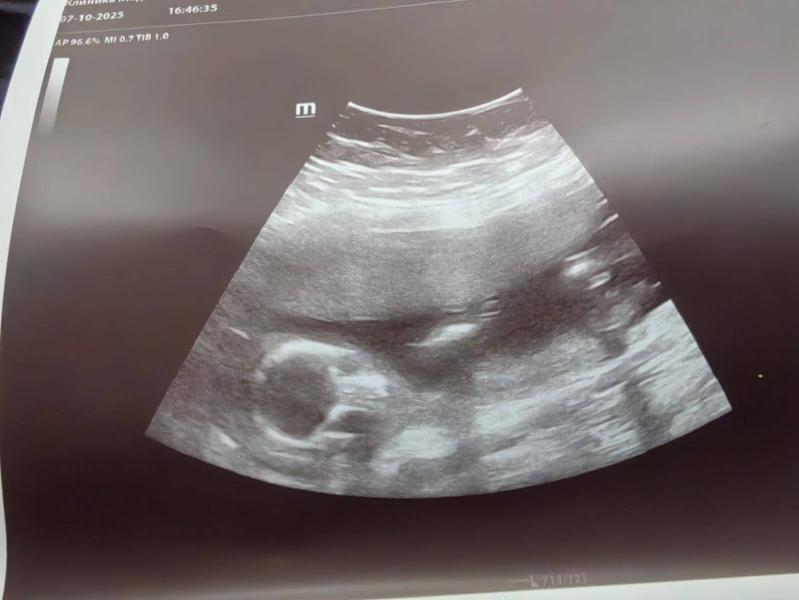

Первые фотки человечка🤗так и не узнали мы кто в "теремочке" живет, очень глубоко сидит и скромничает. Лежит, посасывает палец. Есть предположение что девочка, потому что отчетливого писюна не увидела, как это было у сына. Низкая плацентация сохраняется, перекрывает немного зев.

Девочка вероятнее всего на уз.